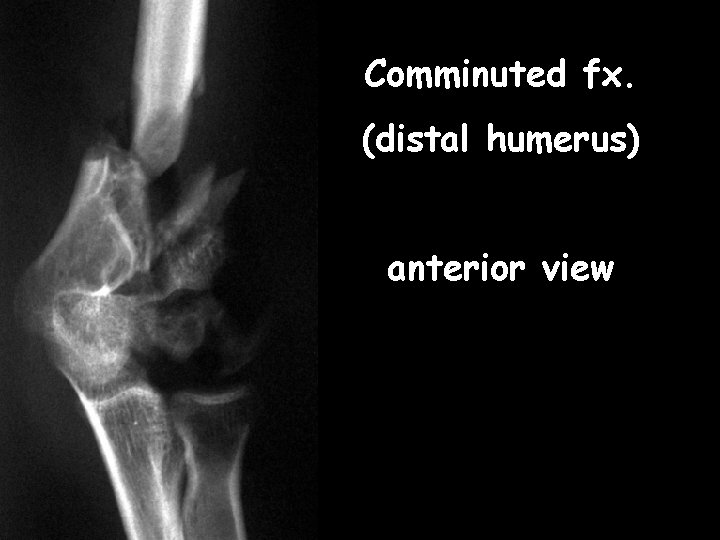

Comminuted fx. (distal humerus) anterior view

Comminuted fx. humerus--lateral view